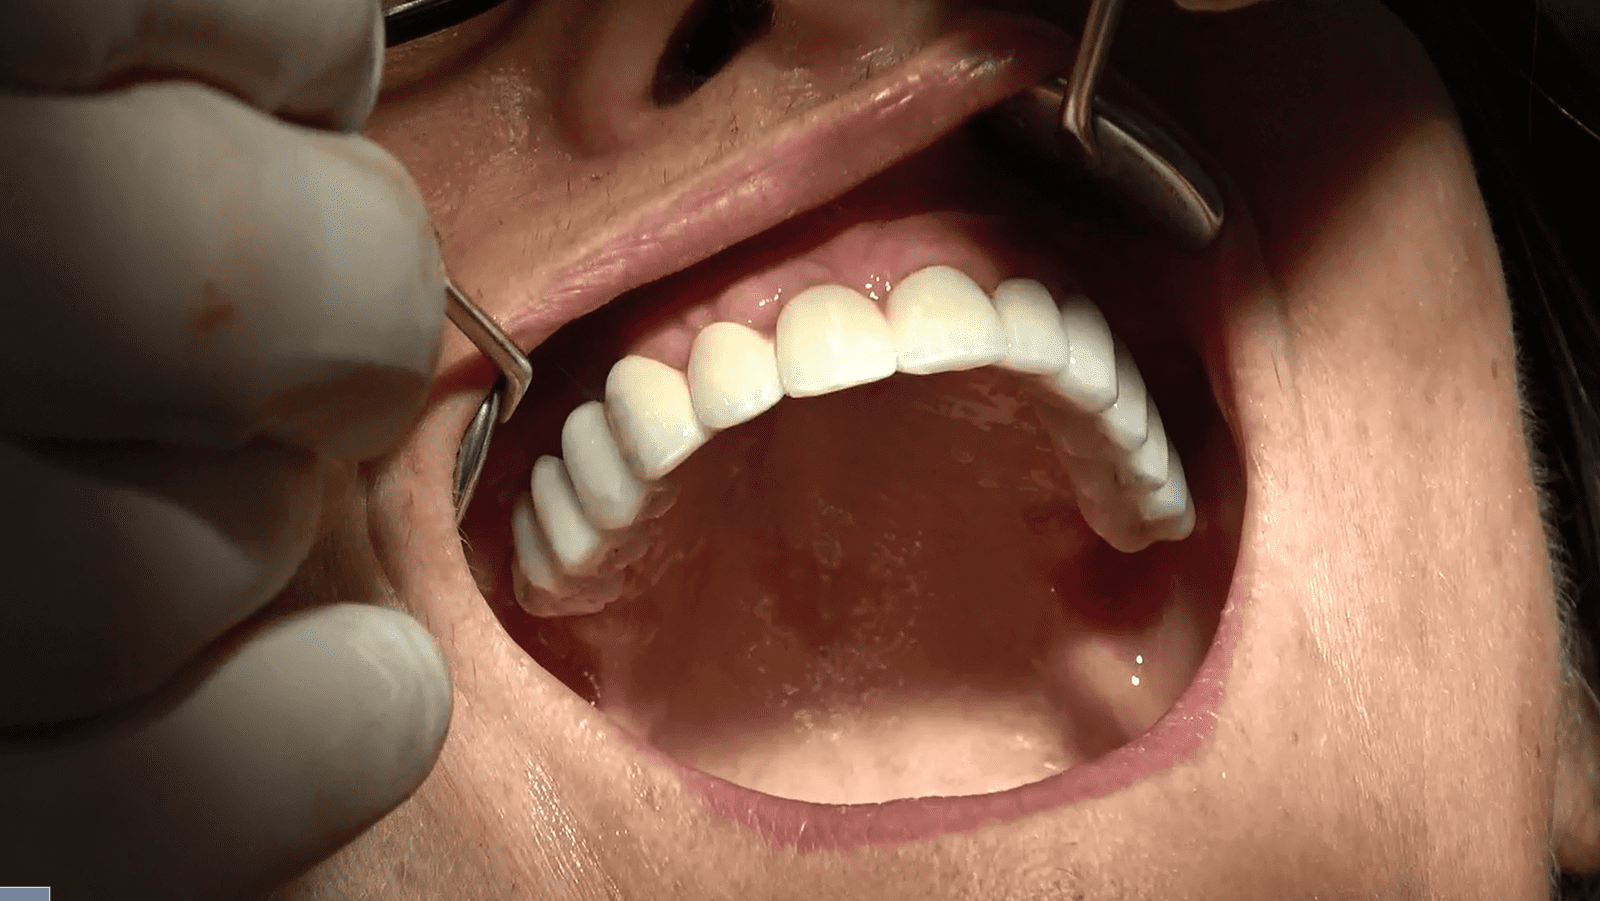

- Carico Immediato: Grazie all’implantologia sottoperiostea, il paziente ha beneficiato del carico immediato, ottenendo denti fissi funzionali in un tempo incredibilmente breve.

Il paziente, dopo un periodo di recupero relativamente breve, ha ripristinato la funzionalità e l’estetica del sorriso. Questo caso dimostra come l’implantologia sottoperiostea possa essere una soluzione efficace anche per pazienti con atrofia ossea estrema, offrendo risultati duraturi e soddisfacenti.